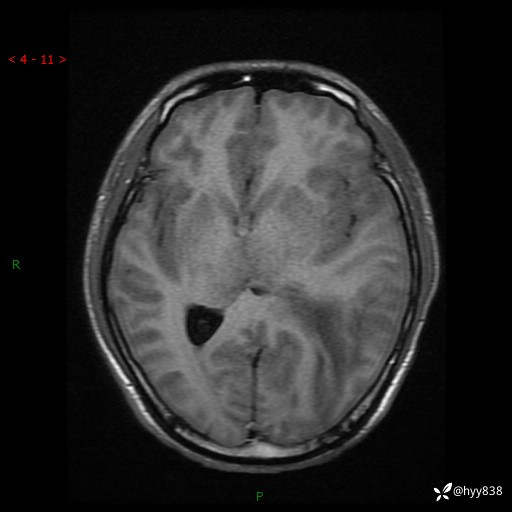

病例年轻小伙,头痛伴呕吐半年,渐进性加重1月。疑难病例,第一次见--结果公布~

性别:男

年龄:21岁

简要病史:头痛伴呕吐半年,渐进性加重1月

颅脑MRI平扫+增强